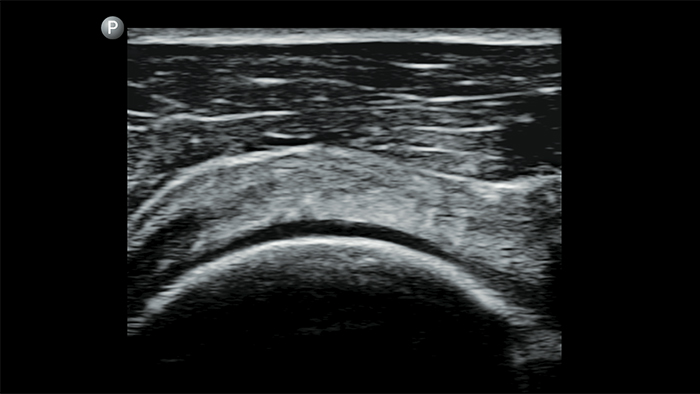

Exceptional ultrasound imaging

Lumify handheld ultrasound offers images that enhance diagnostic confidence.